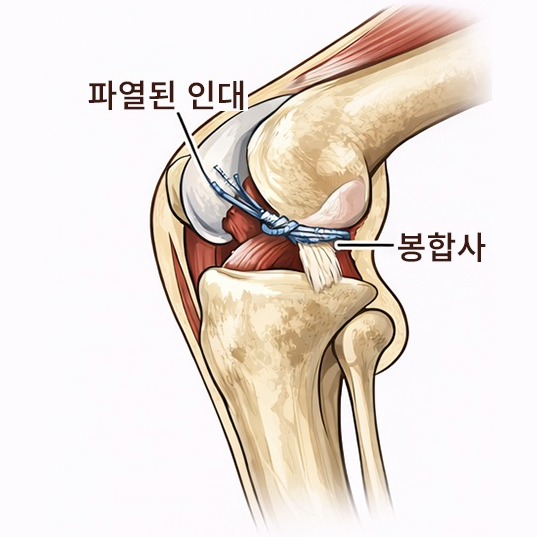

슬개골 탈구 수술은 단순히 빠진 뼈를 제자리로 돌려놓는 수술이 아닙니다.

무릎 관절의 정렬, 뼈의 구조, 연부조직 상태를 종합적으로 판단해 아이에게 맞는 수술 계획이 필요합니다.

슬개골 탈구 수술은 정확한 진단과 수술 환경이 결과를 좌우합니다.

본원은 정형외과 수술을 고려한 장비와 시스템을 갖추고 있으며,

수술 전·후 방사선 검사를 통해 관절 정렬과 수술 결과를 객관적으로 평가합니다.